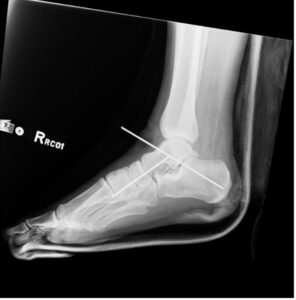

Subtalar Dislocation. Post-surgical reduction lateral. JETem 2024

Subtalar Dislocation. Post surgical reduction lateral. JETem 2024